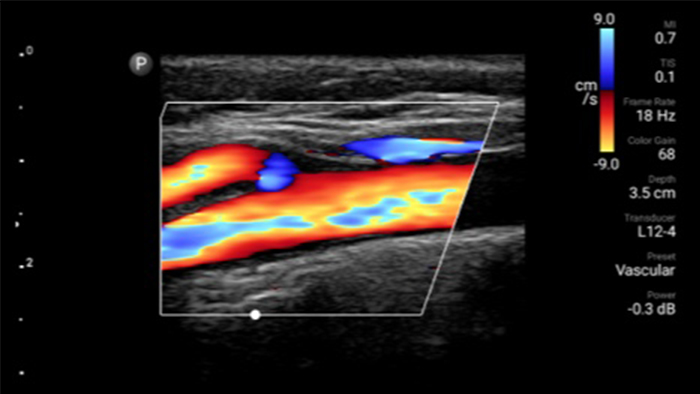

Start treatment with an accurate diagnosis

Lumify helps you see the fine details in muscles, joints, ligaments, tendons and cartilage to make a more accurate diagnosis of injuries.

Get the clarity of larger ultrasound systems with Lumify

SonoCT reinforces real tissue imaging while eliminating random artifacts. This technology produces images superior to conventional imaging in up to 94% of patients.

Lumify L12-4 broadband linear array transducer